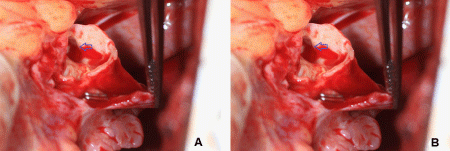

During surgery, we identified the drainage fistula from the right coronary artery that was very difficult to see on angiogram and not seen on echocardiography. This fistulous tract would have bled extensively if damaged or creating more shunting phenomenon affecting patient’s hemodynamic profile once the main fistula was closed. We used a surgical approach of ligation of the giant fistula with Prolene sutures in a double layer at both ends, one end from the fistula tract into the right atrium and the origin of the fistula tract (distance of 2cm measured per TEE). The closure was successfully tested by administering the antegrade cardioplegic solution, and TEE showed no flow in the large fistula body after the procedure per continuous wave Doppler and color Doppler (Figure 5A). TEE Live 3D Zoom from right atriotomy view also confirmed thrombosis in the giant fistula aneurysm (Figure 5B).

Figure 5a TEE ME Bicaval View with color Doppler after fistula ligation procedure. Red and green arrows indicate no blood flow in distal left main coronary artery fistula and giant fistula aneurysm respectively.

LA: Left Atrium; RA: Right Atrium; IAS: Interatrial septum

Figure 5bTEE Live 3D Zoom from Right Atriotomy View after fistula ligation procedure. Blue and red arrows indicate thrombosis in distal left main coronary artery fistula and giant fistula aneurysm respectively.